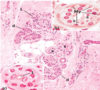

photo on the bottom

- from left to right

- the epidermal ridges are normal in the last 1/4 on the right side, the ridge gets very deep.

- this is where the psoriasis starts

byopsy of a skin graft found the following. What is this indicative of?

condtion, composition

squamous cell carcinoma

- condition

- dermal invasion by abnormal cells of the epidermis

- composition

- pleomorphism (structural changes in cell) of tumor cells

- keratinization within the cells results in abundantly pink cytoplasm, epithelial pearls